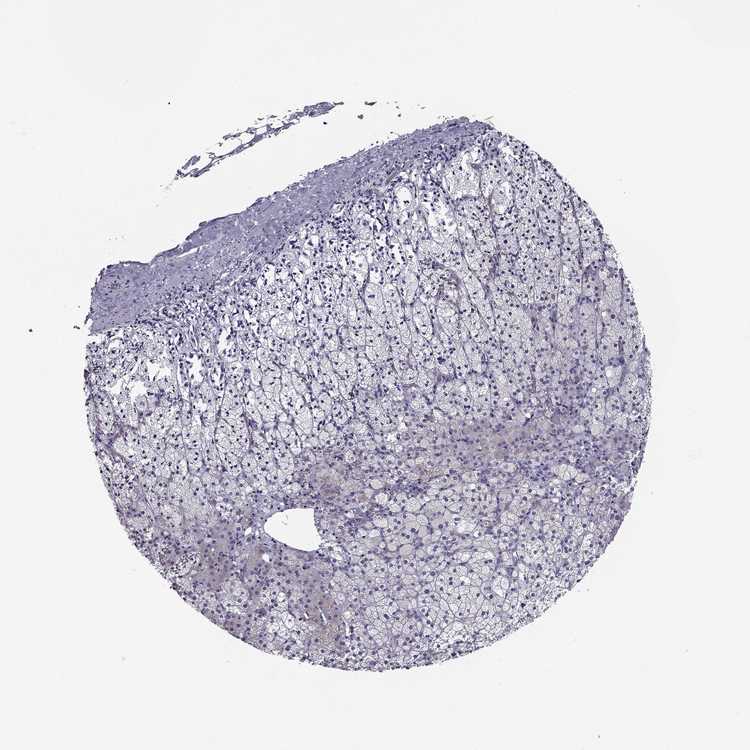

Adrenal gland

ADRENAL GLAND - Expression summary

ADRENAL GLAND - Antibody stainingi

Antibody staining in the annotated cell types in the current human tissue is reported as not detected, low, medium, or high, based on conventional immunohistochemistry profiling in selected tissues. This score is based on the combination of the staining intensity and fraction of stained cells.

Each image is clickable and will lead to virtual microscopy that enables deeper exploration of all samples and also displays staining intensity scores, fraction scores and subcellular localization as well as patient and tissue information for each sample.

Antibody HPA006135Antibody HPA071007

Glandular cells Not detectedLow